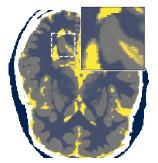

Figure 5 shows an example of a spatio-temporal regularization parameter-map which was estimated using the proposed approach for an acceleration factor of . The network estimates the regularization parameter-map to be pointwise relatively consistenly higher than the spatially required regularization. This result is in fact expected as the temporal dimension is the one for which the gradients of the images are the sparsest because of the high temporal correlation. Further, we see how the network consistently predicts both the spatial regularization as well as the temporal regularization to be less strong in the area where most of the movement is expected, i.e. in the cardiac region.